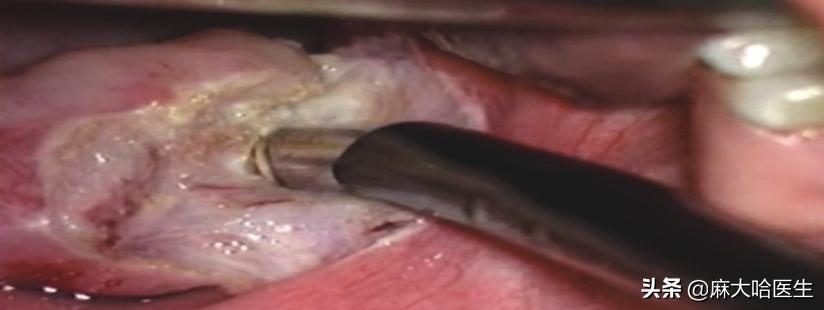

常见的手术方式:1.扁桃体剥离术:门诊手术常用的切除方法;2.等离子融切技术:目前临床使用较多,具有微创、出血少的特点;3.扁桃体挤切术 。

等离子技术切除扁桃体